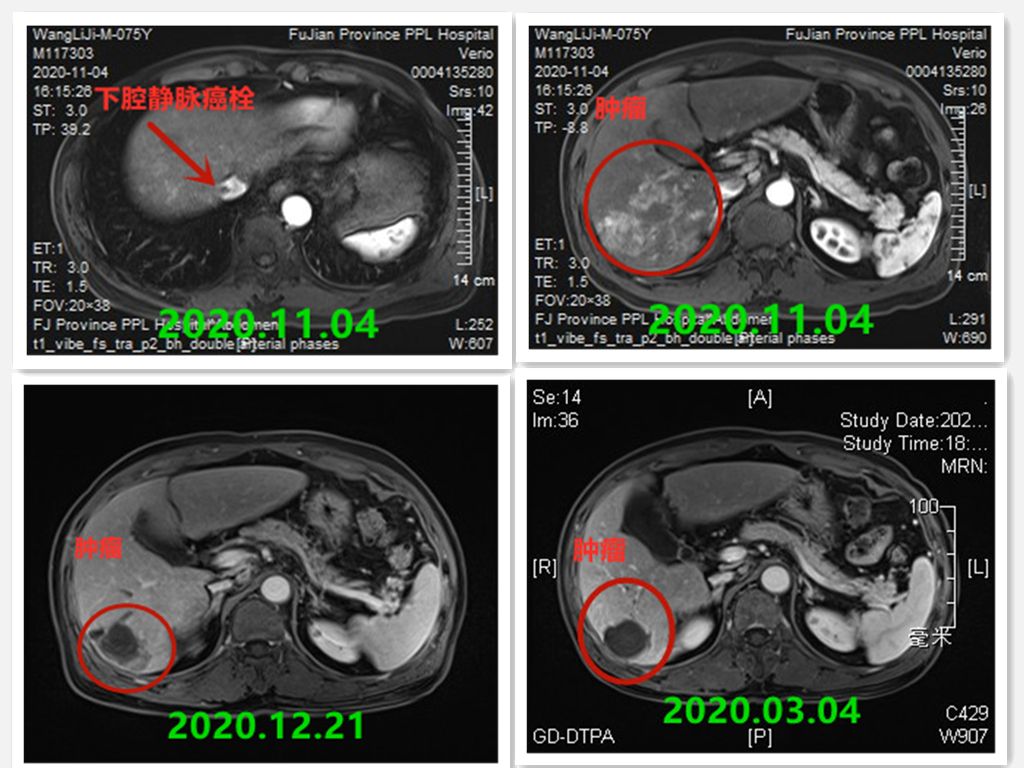

古稀之年的患者老马(化名)体检发现甲胎蛋白升高,通过进一步检查确诊为肝癌,伴有肝静脉癌栓。通过肝胆胰肿瘤MDT(多学科诊疗)团队的努力,患者经过前期的肝脏TACE、免疫、靶向治疗后肿瘤缩小,再予以下腔静脉癌栓放射治疗后癌栓回缩坏死,肿瘤指标直线下降,最终根治性切除右肝后叶和肝右静脉癌栓,术后病理提示标本内未见肿瘤细胞,目前老马仍在接受后续巩固治疗中。